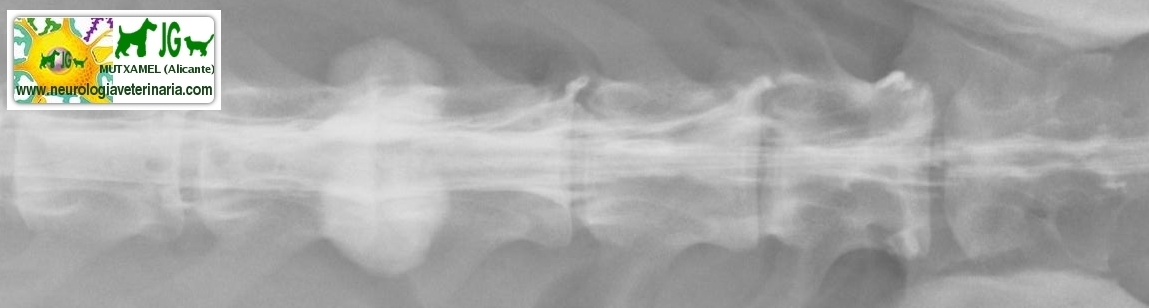

Radiografía con contrastes: mielografía por saco dural | |||||||||

![]() por Juan M. Griñán. Veterinario ![]() comparativa entre una mielografía (mostrando la aguja) y una resonancia magnética, secuencia SE T1w (mostrando donde está el saco dural, sitio para la inyección del contraste). Nótese la extravasación del contraste yodado en la mielografía. | |||||||||